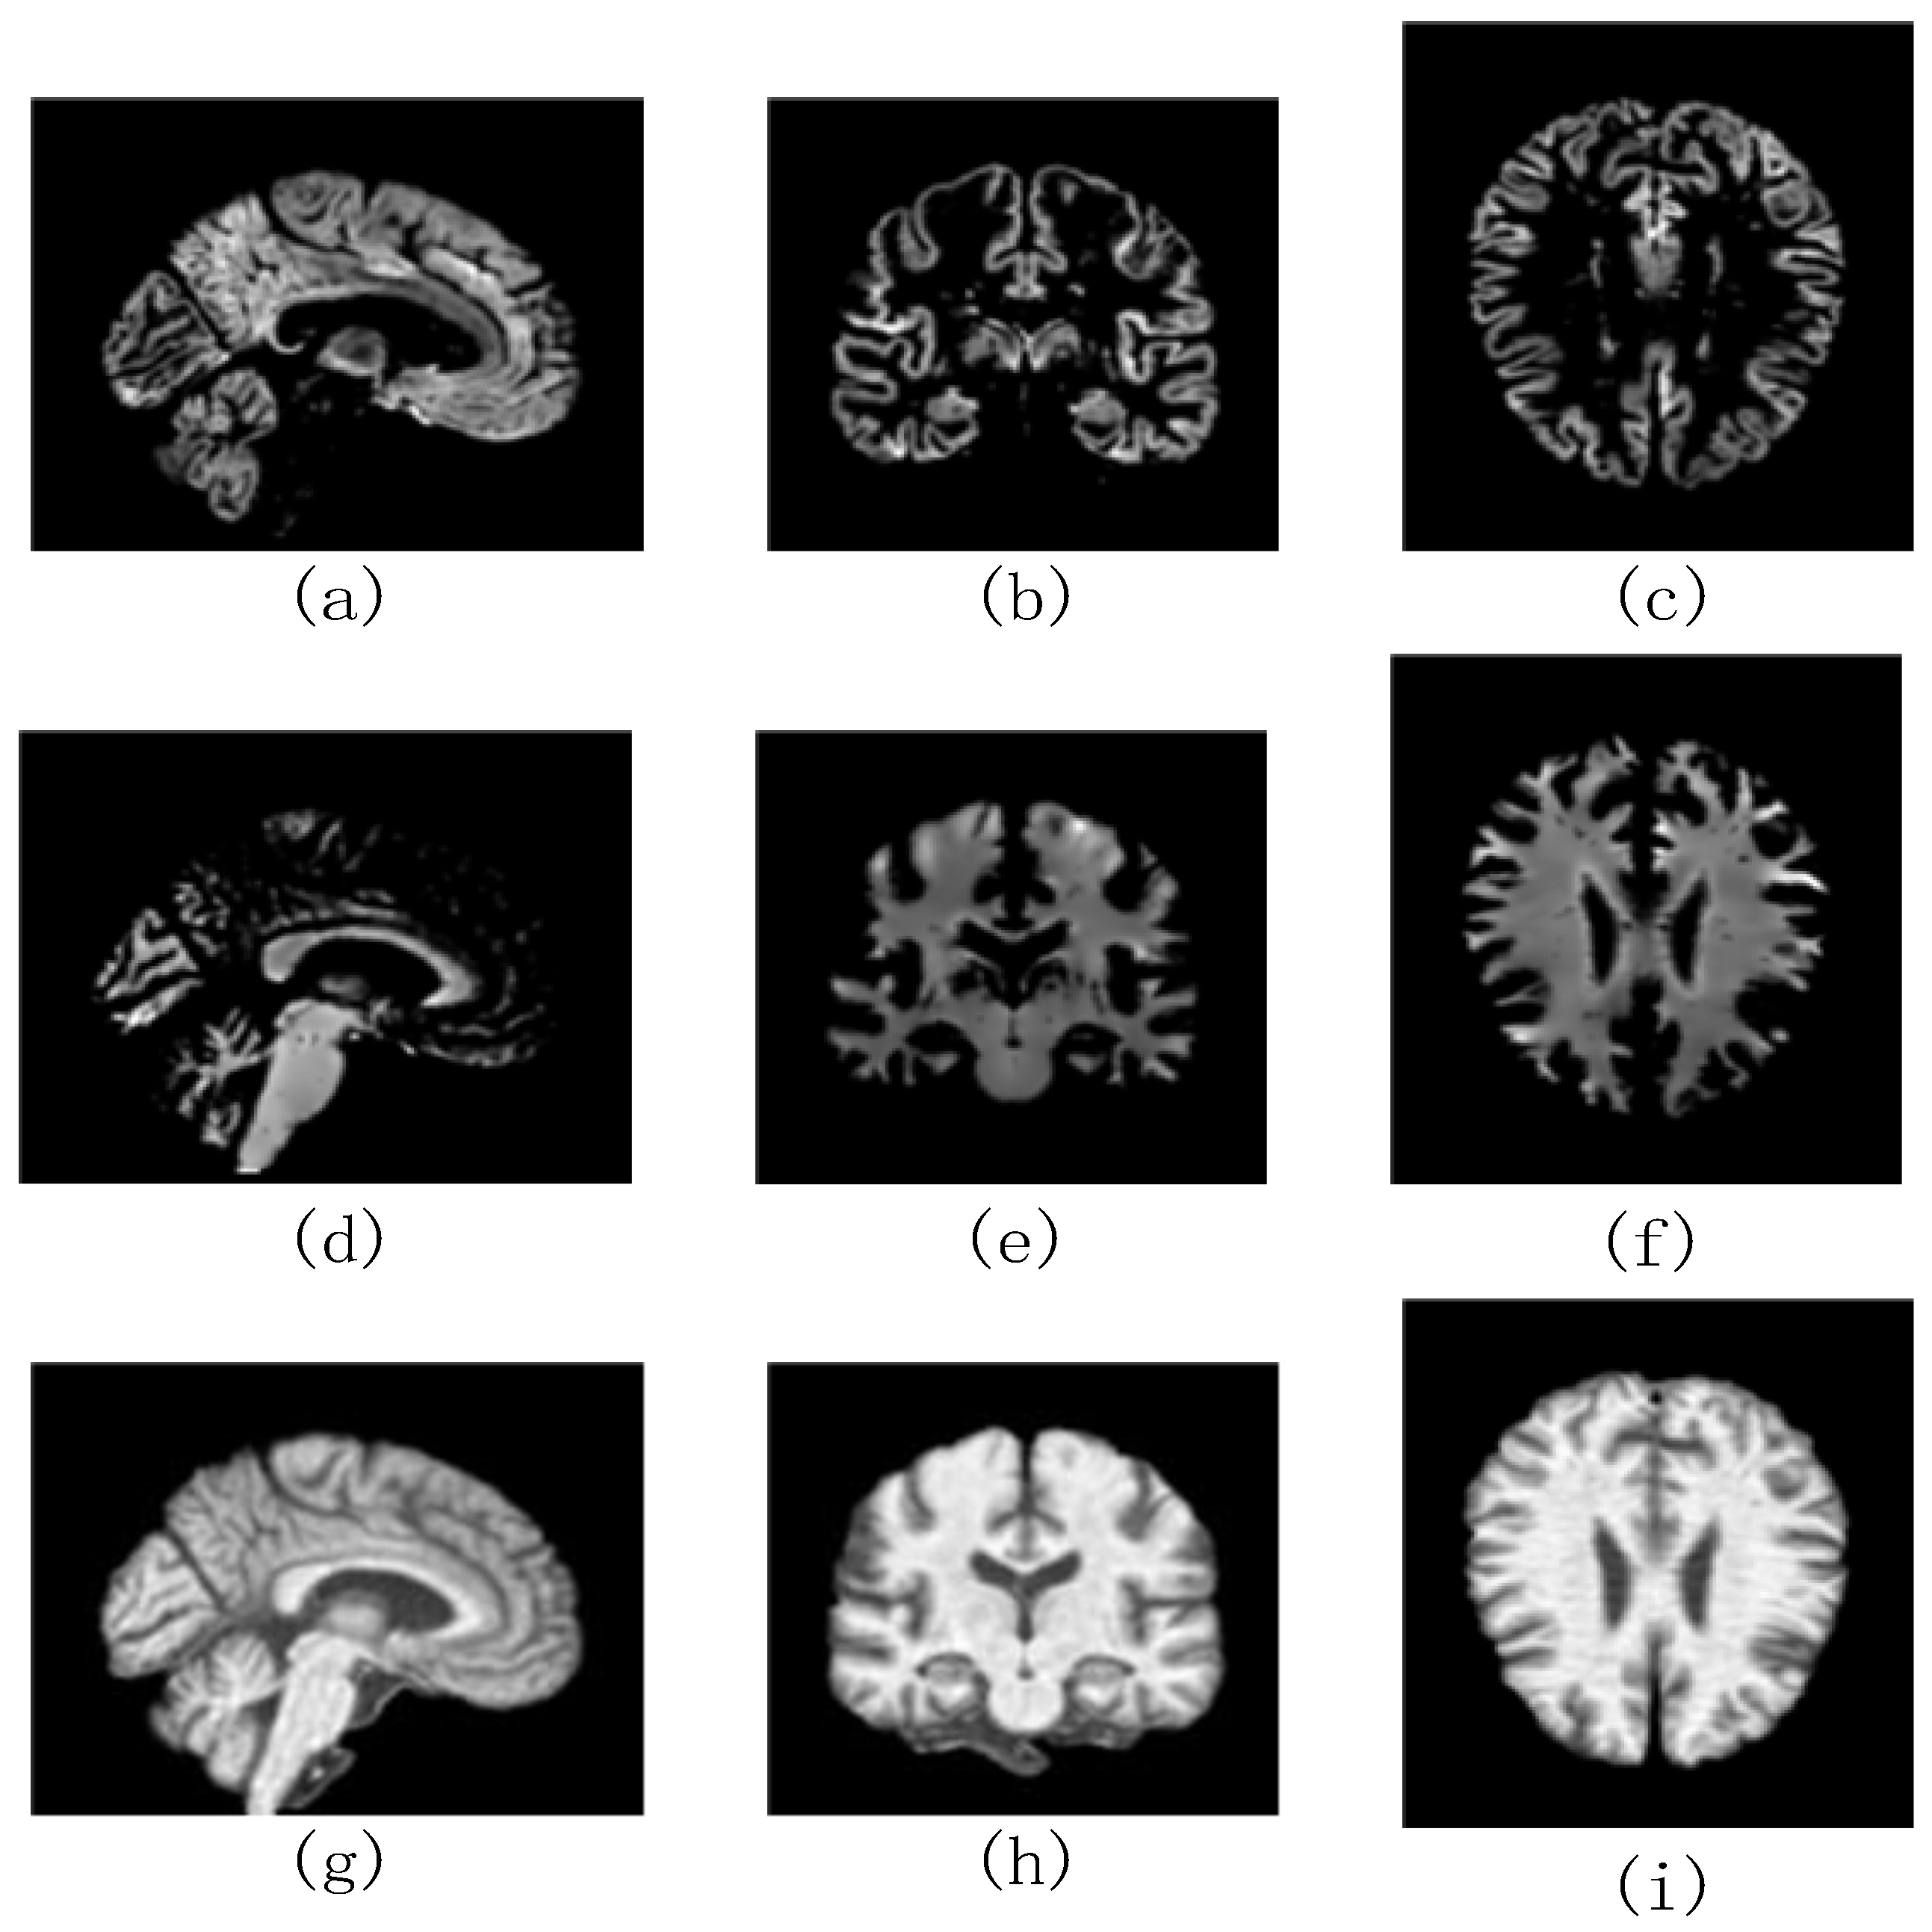

3.2.1. MRI Data Processing Flow

3.2.2. The Choice of the Most Informative Slices